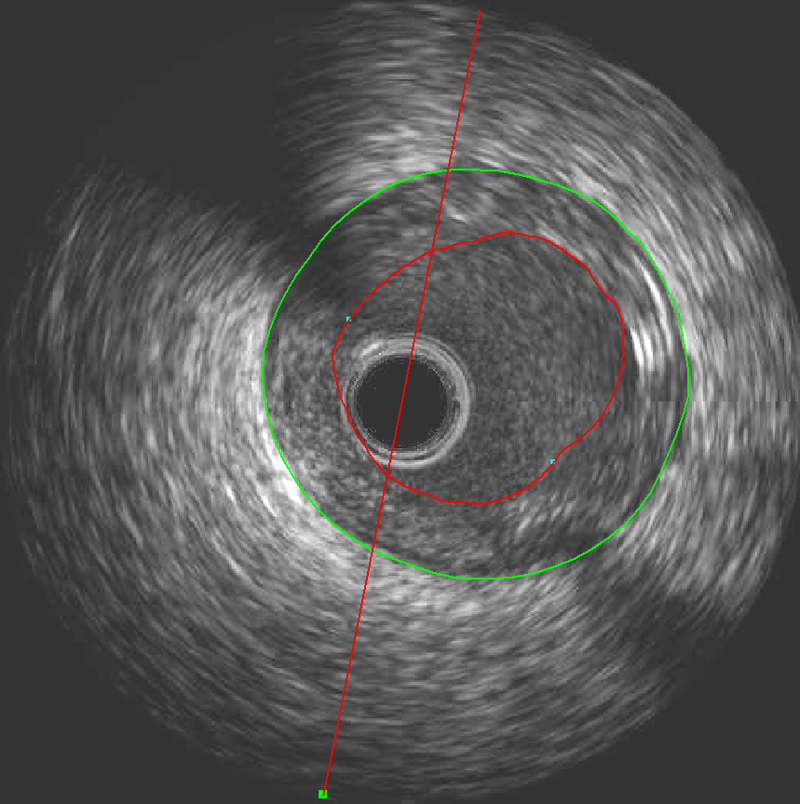

The innovative, vendor-independent post-processing solution for your offline evaluation of IVUS and OCT studies.

IVUS provides time-saving detection of lumen, stent and vessel borders in addition to powerful and fast editing. While OCT provides a fast and intuitive workflow for automatic stent struts detection with an easy thin cap analysis.

QIvus provides a highly detailed report including IVUS results with tissue characterization results, OCT/OFDI stent struts and OCT/OFDI vulnerable plaque.

Intravascular is an innovative, vendor-independent solution for the assessment of offline information from images collected during coronary intervention. In addition it allows for quantitative plaque parameters from grayscale IVUS and detailed stent information on numerous stent struts from OCT.